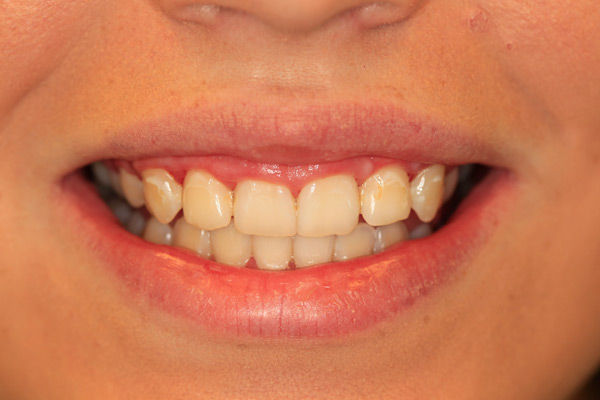

Case Study 9

Problem: This young lady had excessive gum tissue making her teeth appear short.

Plan: Our plan… we sculpted and removed the excessive tissue with the laser.

It’s the small and simple things that make the biggest impact.